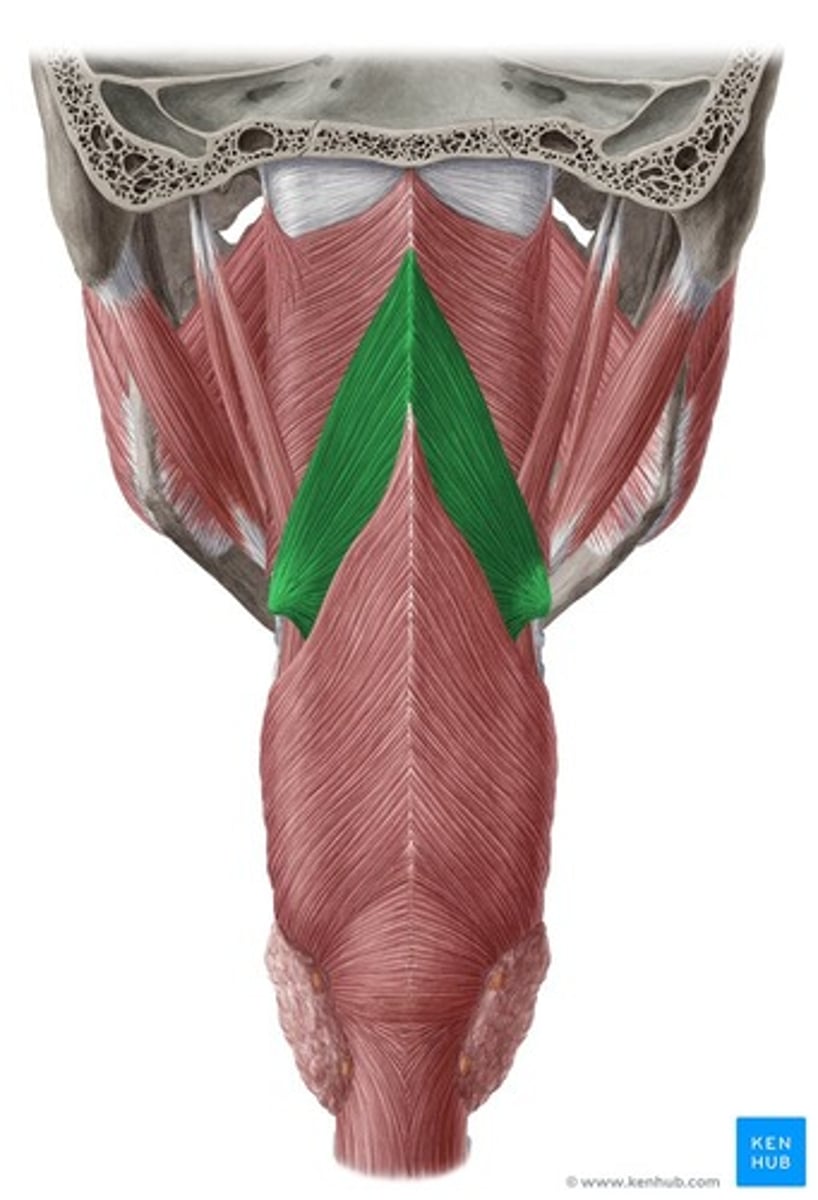

Middle Constrictor Figure

Middle Constrictor Description

Somewhat fan shaped

Origin - hyoid bone

Course - fan out posteriorly and medially

Insertion - midline raphe

Action - reduce diameter of pharynx